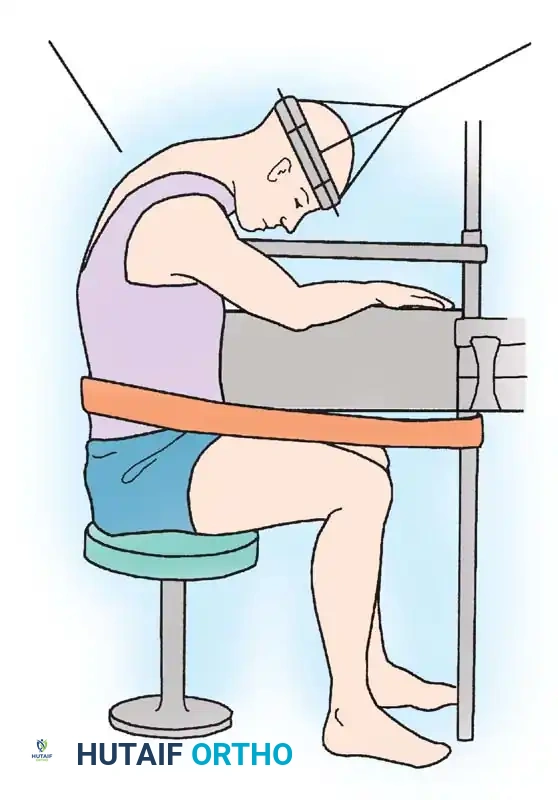

Complex cervical resections often require specialized positioning and stabilization. Halo traction is frequently utilized to maintain alignment during destabilizing osteotomies or tumor resections.

Fig. 41-29: Position of patient for cervical osteotomy—sitting on stool with head suspended by halo and traction. This allows circumferential access and precise alignment control during complex cervical reconstructions.

When performing posterior cervical resections, the osteotomy lines must be meticulously planned to ensure stability if reconstruction is attempted, or to safely widen the canal without plunging into the cord.

Fig. 41-28: Extent of resection of cervical laminae for safe osteotomy. Lateral resections are beveled toward each other so that opposing surfaces are parallel and in apposition after extension osteotomy.